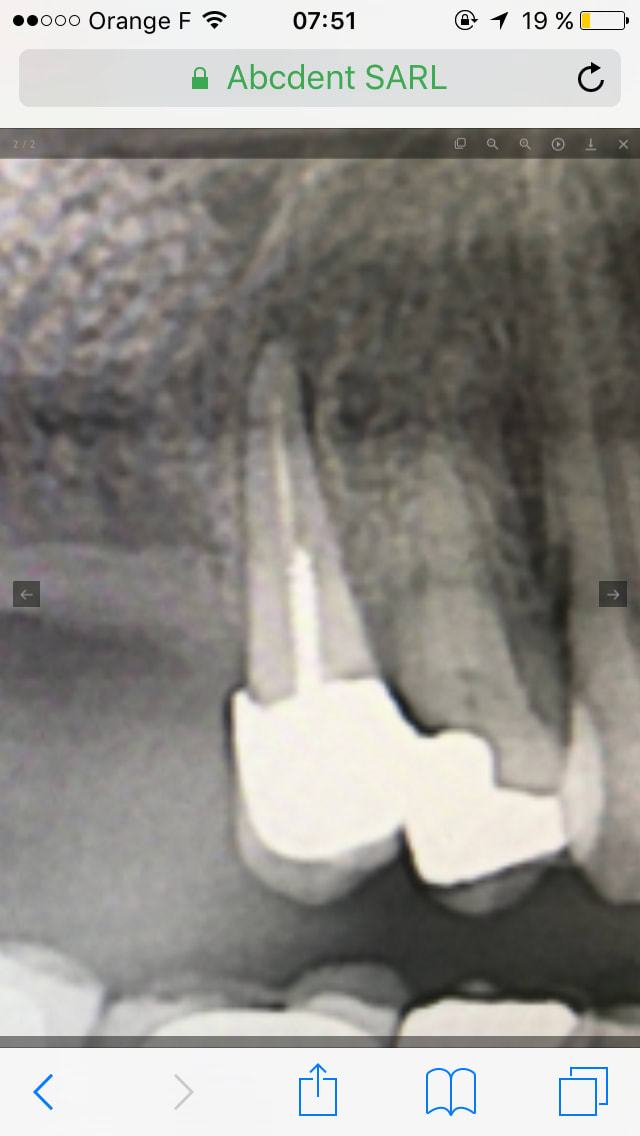

Je trouve que c'est très propre à la radiographie.

Par contre, sur la 2nde radiographie, je serai "ennuyé" de faire un sinus lift avec une image apicale sur 15

Non, ca ne m'inquieterais pas, parfois la membrane ne bouge pas (plus epaisse, patient ne respire pas fort, pas le bon jour...), a ce moment j'essaie de verifier son integrite visuellement. En tout cas vu la radio du premier cas aucune inquietude, on voit bien un volume defini, c'est donc qu'il n'y a pas de dechirure. Sur la deuxieme, la qualite est trop mauvaise, franchement je ne vois rien.